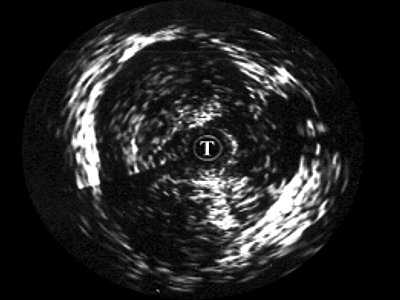

Четко визуализируются патологические образования в паренхиме (рис. 4). В зоне стриктуры мочеиспускательного канала определяется различной протяженности и глубины фиброзная ткань в виде гиперэхогенных участков.

Рис. 4. Эхограмма простатического отдела уретры.